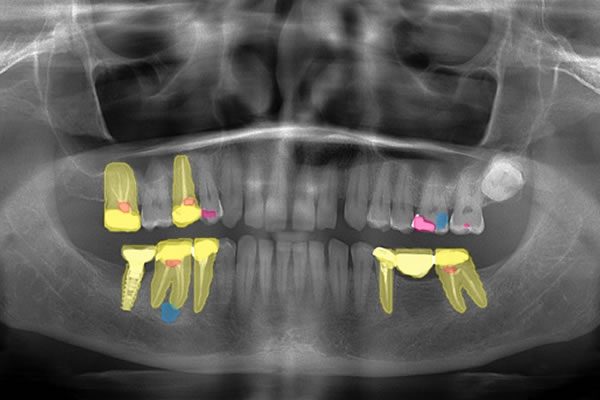

VELMENI for Dentists® 2D

VELMENI is as easy to use as it is powerful. Scan 2D radiographs to increase detection accuracy by 30%. FDA cleared for 2D Panoramic, Bitewing and Periapical X-Rays.